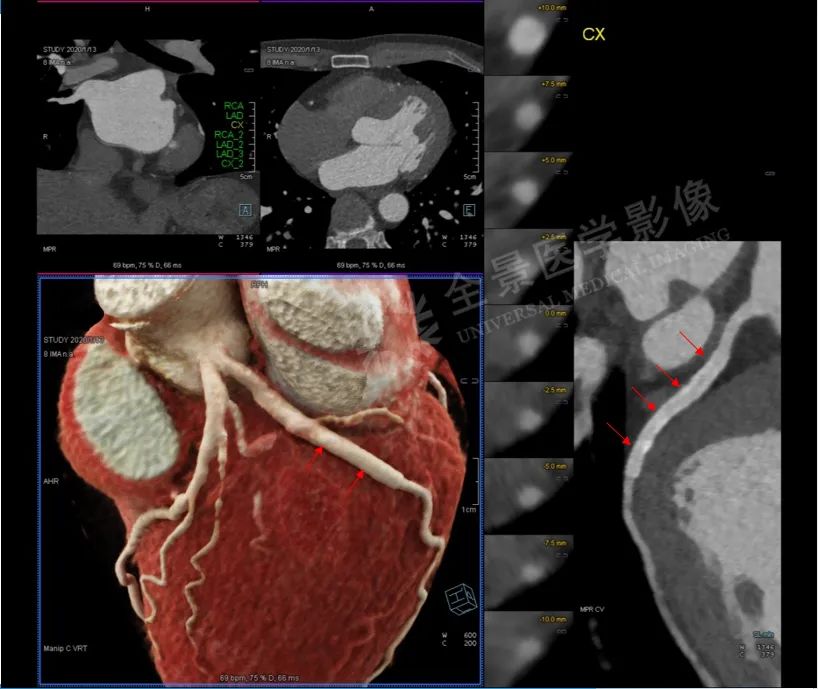

当分别进行完动脉和静脉CT血管重建后,发现患者颈部肿块由颈总动脉供血,强化非常明显,肿块的上方发出两根纤细的颈内动脉和颈外动脉。

同时在肿块的表面又有许多新生的静脉血管团注入上腔静脉。

随后全景医生将动静脉图像叠加融合后,在西门子Syngo.via医学影像后处理系统(VB20版)处理得到颈部动静脉的CT三维图像,并使用电影级的三维可视化实影渲染技术(cVRT),逼真显示出肿块内动脉与静脉的走行关系与三维结构。

经过一系列后处理,肿块血供解剖信息一目了然。

再进行剖面重建并将动脉静脉标识为不同颜色,直观显示出这个肿块内穿行着颈总动脉,并发出“蔓藤样”迂曲的动脉血管网,表面覆盖着静脉血管团,然后汇入上腔静脉(见下图),诊断呼之欲出,这是一个罕见的左侧颈部巨大血管瘤。